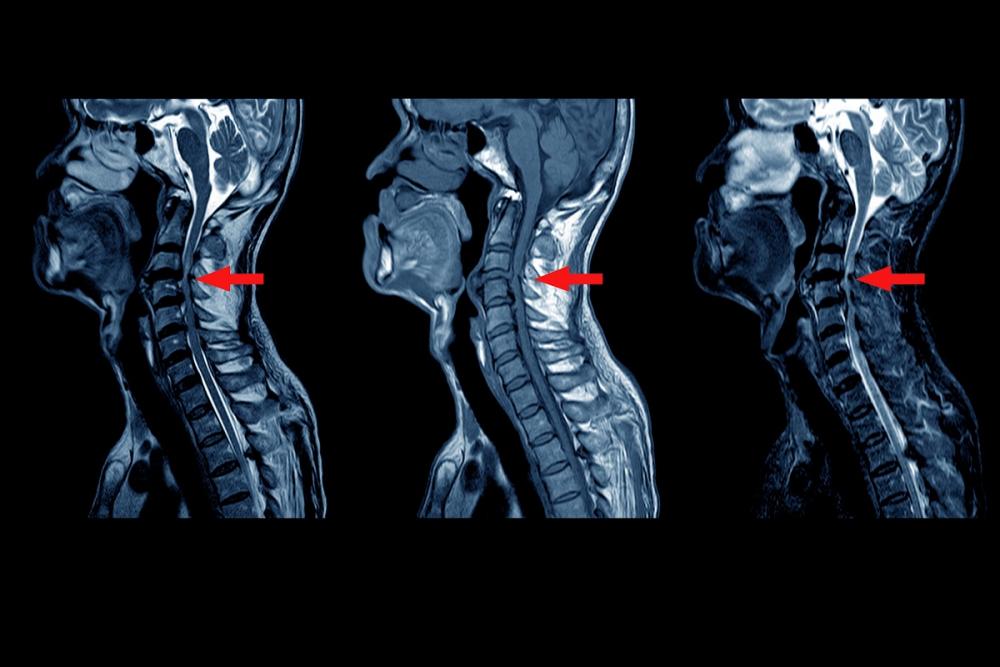

Магнитно-резонансное сканирование крестцово-подвздошных сочленений, пояснично-крестцового отдела помогает выявить ранние изменения целевой зоны. Благодаря компьютерной томографии определяются деформация костных элементов, эрозивные дефекты сочленений.

1. Дорентгенологическая (ранняя). На рентгеновских снимках отсутствуют признаки повреждения КПС, хребта. На МРТ заметны проявления сакроилеита.

3. Гормональная терапия. При выраженном болевом синдроме требуется применение глюкокортикостероидов. Уколы делают в интересующую область под контролем магнитно-резонансной, компьютерной томографии.